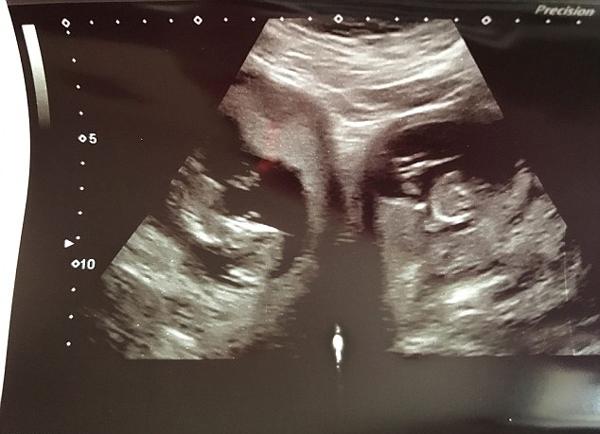

"Chúng tôi phát hiện ra điều này trong lần siêu âm 20 tuần và các bác sĩ đã giải thích nó cực kỳ hiếm", Jennifer chia sẻ.

Jennifer phát hiện mình mang 2 thai ở 2 bên tử cung.

Đặc biệt hơn, thông thường mẹ có hai tử cung nếu mang thai thì em bé sẽ nằm ở một trong hai bên tử cung nhưng Jennifer lại mang thai đôi và hai bé nằm riêng rẽ ở hai bên tử cung khác nhau. Trường hợp này trên thế giới chỉ được ghi nhận chưa đến 100 ca, còn ở Anh thì còn ít hơn nữa.